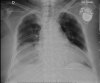

Intrathoracic kidney is a very rare finding, representing less than 5% of all renal ectopias. Because of the location of the liver, thoracic kidney on the right side is much less common than thoracic kidney on the left side. Although an increasing number of case reports are being published in the literature, few describe the impact of the ectopia on kidney function. We report the case of a woman with intrathoracic right kidney and chronic kidney disease that was initially misdiagnosed as pneumonia because of its presentation on chest x-ray. We highlight the need to including this condition in the differential diagnosis[2] as the literature rarely links it to changes in kidney function.